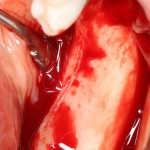

Остеопластика — всего одна операция.